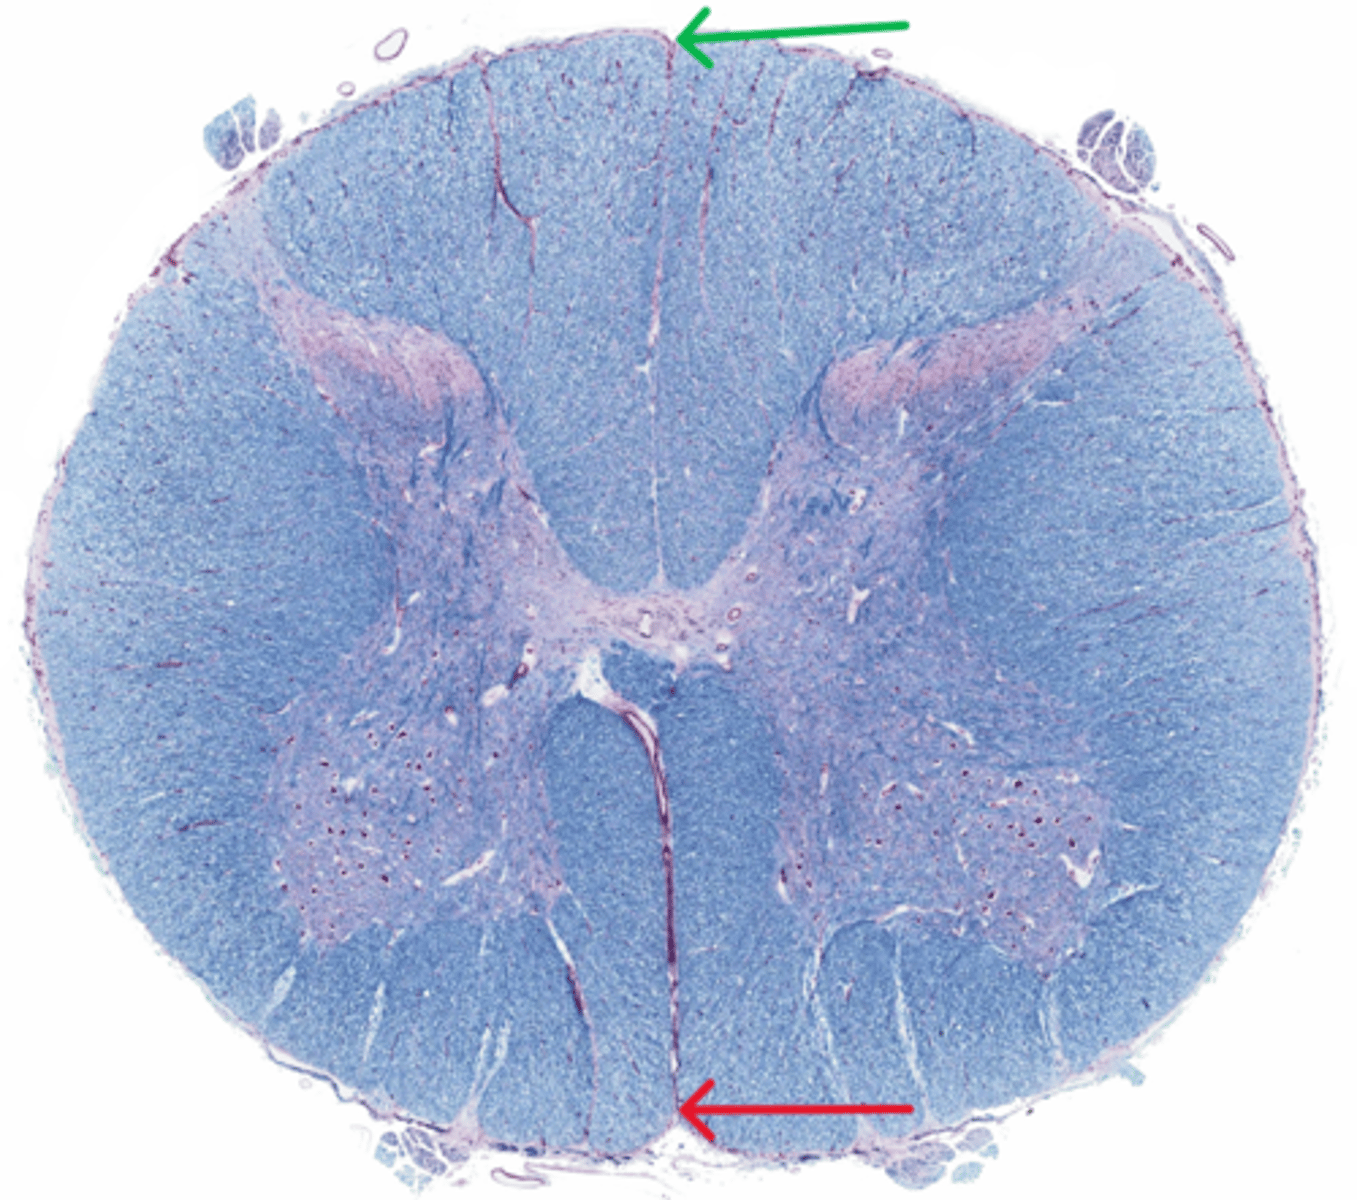

Posterior funiculus

Green

Anterior funiculus

Yellow

Lateral funiculus

Red

Posterior median sulcus

green

Anterior median fissure

red